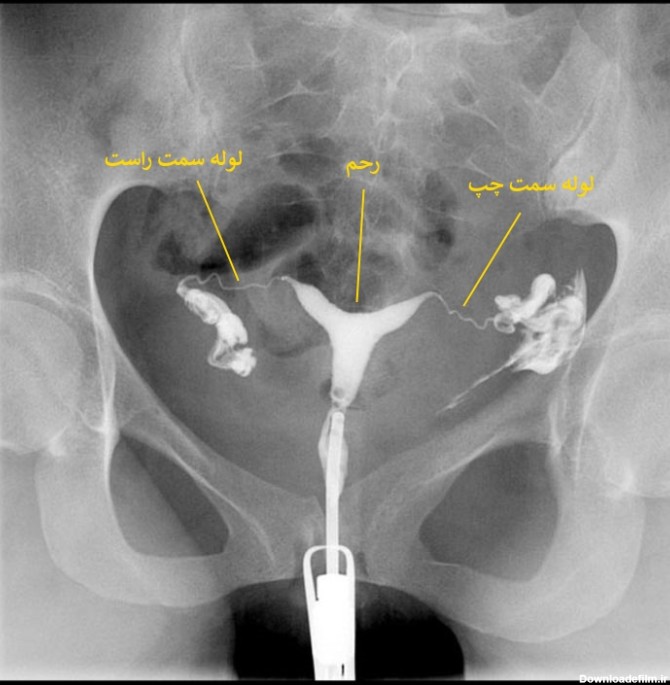

عکس رنگی رحم یا هیستروسالپنگوگرافی روشی جهت تصویربرداری با اشعه ایکس از رحم و لوله های آن است که با تزریق ماده حاجب به آن، در تصاویر رادیولوژی رحم را رویت پذیر کرده و بررسی ناهنجاریهای آن را توسط رادیولوژیست ممکن میسازد.

"هیستروسالپنگوگرافی" یا "عکس رنگی رحم" یک روش تصویر برداری است که به پزشک کمک میکند تا با استفاده از اشعه ایکس داخل رحم و لوله های فالوپ را مشاهده کند. این